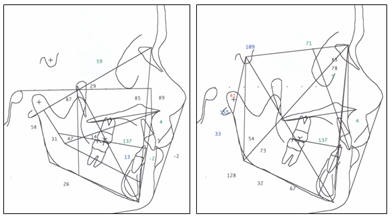

B) Telerradiografía

de perfil.- previo al inicio del tratamiento

B) Fig.

4.-Telerradiografía de perfil, previo al inicio del

CEFALOGRAMAS DEL PACIENTE: Ricketts - Jarabak |

Fig.

5.- Cefalograma del paciente según Ricketts y Jarabak. |

Las medidas

cefalométricas revelaron un ángulo SNA de 83º, un SNB de 77.8 y un

ANB de 5.2º, el ángulo interincisivo tiene 137º, y el incisivo

inferior en relación a APg. Esta a -2 mm, la Base Craneal Posterior

muy grande 41 mm. (fig. 5 y en cefalogramas presentados al final de

esta descripción, antes y al final del tratamiento)

Telerradiografía antes y al final del tratamiento (Fig.

# 23) |

Fig.#

23.-En las telerradiografías antes y al final del

tratamiento podemos destacar especialmente la reducción

del overjet, de tal manera que se ha obtenido una buena

relación entre dentadura superior e inferior, nótese

además la migrasión a mesial de los sectores posteriores

superiores, de tal manera que va a ser necesario

mantenerse a los terceros molares superiores a fin de

que ocluyan con los segundos inferiores. |